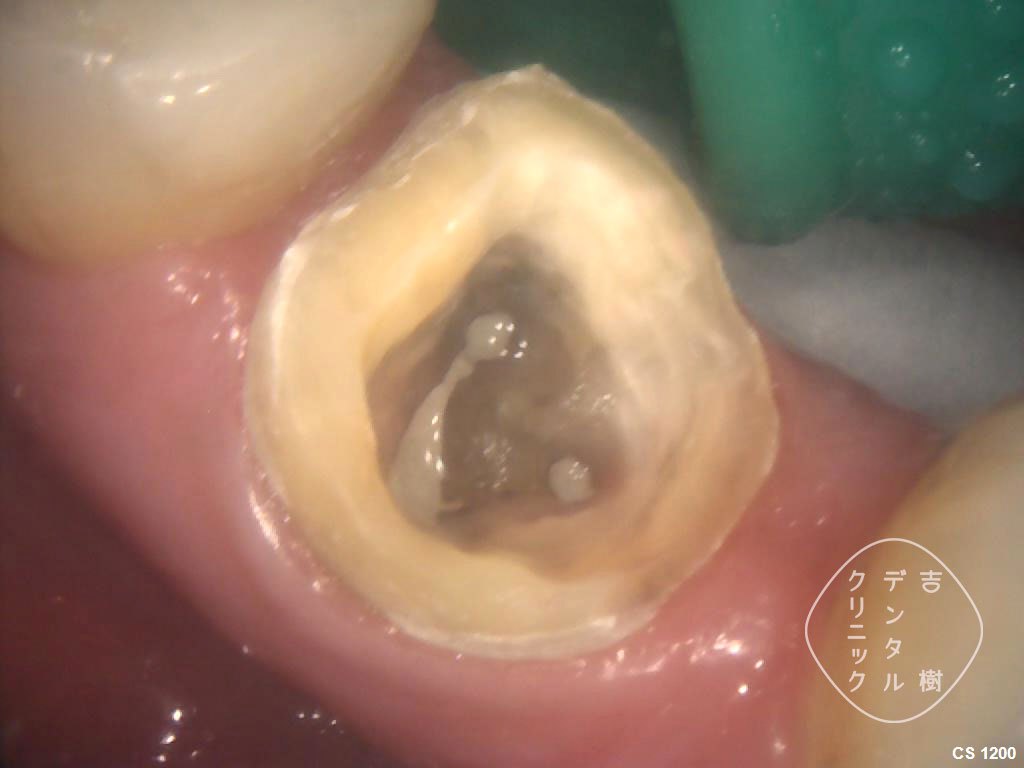

①虫歯で崩壊してしまった奥歯

②「歯冠延長手術」で歯肉を切除した

③「歯冠延長手術」で歯肉を切除した

④歯を修復し、土台を作る治療をする

⑤被せ物を装着し、治療完了